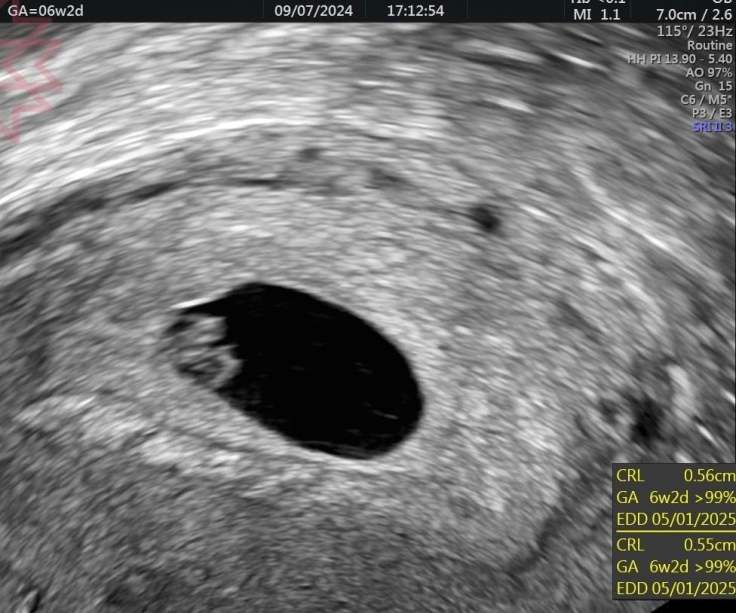

這兩張超音波圖片是同一個媽咪的

6+2週

後面這張是經陰道的超音波